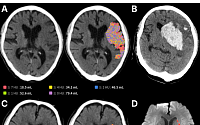

제이엘케이는 뇌졸중 영상 분석 인공지능(AI) 솔루션이 분당서울대학교병원의 실제 임상 현장에서 도입 효과를 나타내고 있다고 22일 밝혔다.

분당서울대병원은 국내에서 뇌졸중 환자를 가장 많이 진료하는 의료기관으로 연간 수천 명 규모의 급성 뇌졸중 환자가 내원하는 상급종합병원이다. JBS-01K를 포함한 뇌졸중 AI 솔루션 패키지를 구독형 모델로 도입한